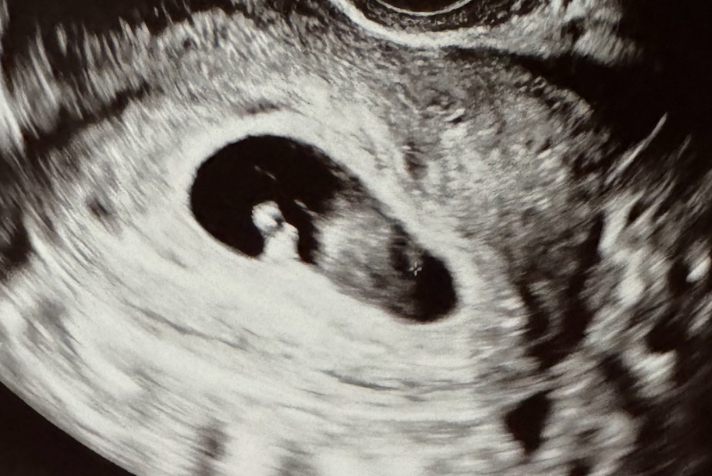

✨임신9-11주차일상/절박유산 진단 그 후/임산부 단축근무,산후조리원 예약?

임신 극 초기 절박유산 진단을 받고 2주간 눕눕 생활을 한 레몬입니다 .. -전편 피비침이 있을때마다 지옥...